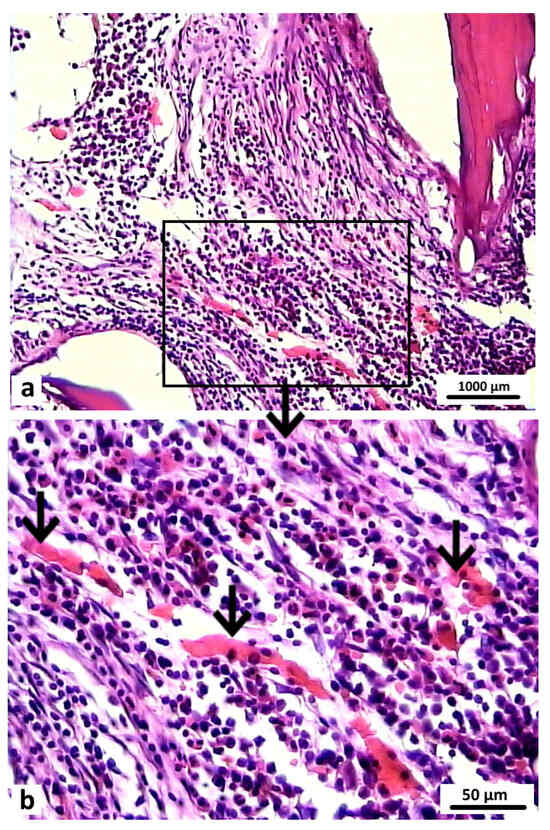

Morphological examination. During the histological analysis after 1 month of observation, the area of the modeled defect could clearly be determined in the rabbits in both groups, which corresponded to the visual picture and CT data.

In the animals in the control group, which had had the osteoplastic matrix implanted in the bone defect area, the graft localization area had clear contours on this section. The control graft structurally resembled cancellous bone tissue with well-developed trabeculae, which were stained pink or red depending on the dye applied (Figure 9a). The control graft was tightly attached to the bone marrow elements (Figure 10a). The perifocal area of the animals in the control group was characterized by signs of periosteal hypertrophy and areas with foci of chondrocyte-like, poorly differentiated cells. The bone defect area was separated from the surrounding tissues by a dense layer of connective tissue.

Figure 9.

Microstructure of materials, Van Gieson staining, 100×: (a) osteoplastic matrix; (b) hybrid polymer.

Figure 10.

Graft localization area in animals 1 month after surgery: (a) control group (1—fragment of the control material–osteoplastic matrix, 2—bone marrow). Hematoxylin and eosin staining; 200×); (b) experimental group (1—elements of experimental material–hybrid polymer; 2—bone marrow; connective tissue fibers are indicated by arrows). Van Gieson staining; 200×.

In the bone tissue samples of the animals in the experimental group, after 1 month of the postoperative period, the entire volume of the bone defect was filled with the hybrid polymer material. This had an amorphous structure and was almost unstained by the histological dyes (Figure 9b). The sections showed that the material adhered tightly to the bone fragments. The experimental sample was separated from the bone marrow elements by a narrow strip of loose fibrous connective tissue (Figure 10b), which also extended to cover the bone defect area.

The perifocal area, as with that in the control group, contained areas filled with chondroid-type cells (Figure 11a). Erosion lacunae in the form of clefts were clearly visible in the area of contact between the compact bone substance and the inner layer of the periosteum. These lacunae occurred both in isolation and accumulated in large groups (Figure 11b). There were no signs of any inflammatory reaction in either the control animals or the experimental group animals.

Figure 11.

Perifocal area in the experimental group animals 1 month after surgery: (a) accumulation of chondrocyte-like cells (indicated by arrows) in close contact with elements of the bone tissue—2, Van Gieson staining: 400×; (b) erosion lacunae in the form of clefts are clearly visible in the contact area of the periosteum inner layer—1 and bone compact substance—2. Van Gieson staining; 200×.

After 2 months of the postoperative period, differences were noted in the signs of reparative regeneration in the graft localization area between the control and experimental group animals. The process of integration of the control material into the surrounding tissues was more intensive. These sections showed structural elements of the osteoplastic matrix, surrounded by a heterogeneous cell-fiber population of fibroreticular tissue and functionally active microvessels (Figure 12).

Figure 12.

Graft localization area in the control group animals 2 months after surgery. Structural elements of the osteoplastic matrix surrounded by the heterogeneous cell-fiber population of the fibroreticular tissue. Functionally active microvessels (indicated by arrows), Van Gieson staining: (a) 40×; (b) 200×; (c) 400×.

After 2 months of the postoperative period, the sections of bone tissue in the experimental group animals demonstrated poorly differentiated groups of cells and connective tissue fibers, and single microvessels in the graft localization area (Figure 13).

Figure 13.

Graft localization area (hybrid polymer) in animals in the experimental group, 2 months after surgery: 1—experimental material; 2—poorly differentiated cells; 3—connective tissue fibers. Van Gieson staining; 400×.

Newly formed bone tissue was found in the area of graft contact with the bone marrow and in the bone defect area in the animals in the experimental group (Figure 14). At 2 months after surgery, the foci of chondroid differentiation in the perifocal area remained in both the control and experimental group animals.

Figure 14.

Graft localization area (hybrid polymer) in animals in the experimental group, 2 months after surgery (1—newly formed bone tissue, 2—bone marrow, 3—implant zone. The area of the bone defect is indicated by a curly bracket). Hematoxylin and eosin staining: (a) 40×; (b) 200×.

After 6 months, the bone tissue samples of rabbits in the control group showed that the defect was completely filled with the bone regenerate and the surface was covered with a thickened periosteum. In the area of the bone defect bed, the regenerate was represented by fresh bone tissue. Functionally active osteoblasts were identified on the surface of the developing bone trabeculae. The structural elements of the osteoplastic matrix were preserved, but these were thinned and had signs of resorption. The graft localization area in these animals in the control group at 6 months after surgery was represented by reticulofibrous tissue with thin bone trabeculae (Figure 15).

Figure 15.

Area of osteoplastic matrix localization in animals in the control group 6 months after surgery. Reticulofibrous tissue with thin bone trabeculae (indicated by arrows). Hematoxylin and eosin staining: (a) 200×; (b) 400×.

Histological preparations of bone tissue sampled from animals in the experimental group during this observation period showed that the defect was also completely covered by lamellar bone tissue. In the graft localization region, small areas filled with experimental material were found in close contact with heterogeneous groups of cells and microvessels (Figure 16).

Figure 16.

Graft localization area in animals in the experimental group 6 months after surgery (1—hybrid polymer), 1000×: (a) heterogeneous group of cells (indicated by white arrows); (b) microvessels (indicated by black arrows) in close contact with small particles of the hybrid polymer. Hematoxylin and eosin staining.

Therefore, the data obtained in the morphological examination demonstrated that the rate of bone tissue regeneration observed with the hybrid polymer was comparable with the rate observed with the osteoplastic matrix. The results of this long-term investigation enable us to conclude that the graft samples made of hybrid polymer material were safe and biocompatible. Therefore, this material (PHB) can be used to replace bone defects to help optimize osteogenesis in the case of bone tissue damage. It can be assumed that the graft indirectly influences the process of aseptic inflammation in the wound and stimulates the proliferation of osteogenic cells.